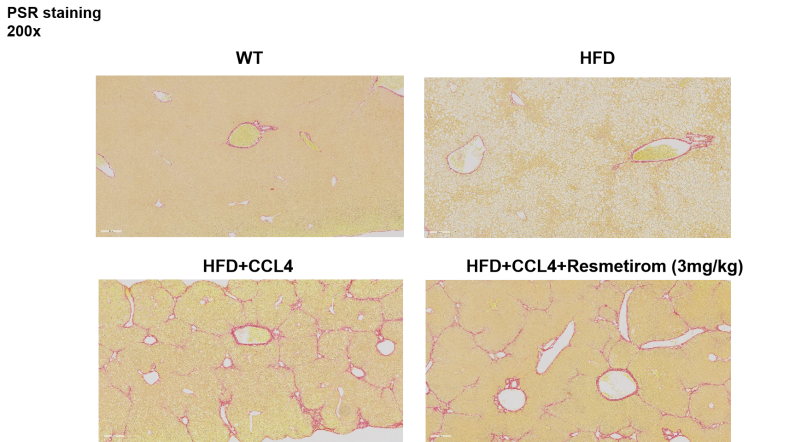

HFD+CCl4诱导的 MASH(NASH)小鼠药效数据 图2 给药期间小鼠体重的变化曲线及试验终点肝重指标 HFD诱导12-16周的小鼠体重和肝重均升高,其中体重可达40g以上。治疗四周后,Resmetirom可显著降低动物体重和肝重。*P<0.05,与高脂饮食对照组差异显著。数据表示为平均值±标准误。*P<0.05视为具有统计学意义,采用单因素方差分析。 图3 小鼠总胆固醇(TC)水平、高密度脂蛋白胆固醇(HDL-C)水平及低密度脂蛋白胆固醇(LDL-C)水平 HFD诱导的小鼠均可显著提高血清中TC、HDL-C和LDL-C的水平,治疗中期和试验终点Resmetirom可降低由高脂饮食诱导的血清中TC、HDL-C和LDL-C的水平。数据表示为平均值±标准误,n=5。#P<0.05、##P<0.005和####P<0.001与正常饮食对照组比较;*P<0.05、**P<0.005与高脂饮食+CCL4组比较,采用单因素方差分析。 图4 丙氨酸氨基转移酶(ALT)水平及天门冬氨酸氨基转移酶(AST)水平 治疗期间给予CCL4后检测肝功指标,发现CCL4显著提高了ALT和AST的水平,治疗组的Resmetirom降低了CCL4诱导的血清中ALT和AST水平。数据表示为平均值±标准误,n=5。#P<0.05、##P<0.005与正常对照组比较;*P<0.05、**P<0.005与高脂饮食+CCL4组比较,采用单因素方差分析。 图5 小鼠肝脏病理组织学检测结果:HE染色、NAS评分、ORO染色与PSR染色 4周治疗后,Resmetirom保护了HFD和HFD+CCL4诱导的肝脏脂肪变性和气球样变。蓝色箭头表示脂肪变性,绿色箭头表示小叶炎,黑色箭头表示气球样变。脂肪变性(0-3分)、小叶炎症(0-3分)、气球样变(0-2分)、NAS评分(0-8分)。数据表示为平均值±标准误,n=5。 图6 肝α-平滑肌肌动蛋白α-SMA(Acta2)mRNA及一型胶原蛋白(Collagen 1α1)mRNA的水平表达 4周治疗后,Resmetirom抑制了由HFD+CCL4显著诱导的肝纤维化标志物的mRNA水平。数据表示为平均值±标准误,n=5。*P<0.05,**P<0.005,****P<0.001,采用单因素方差分析。